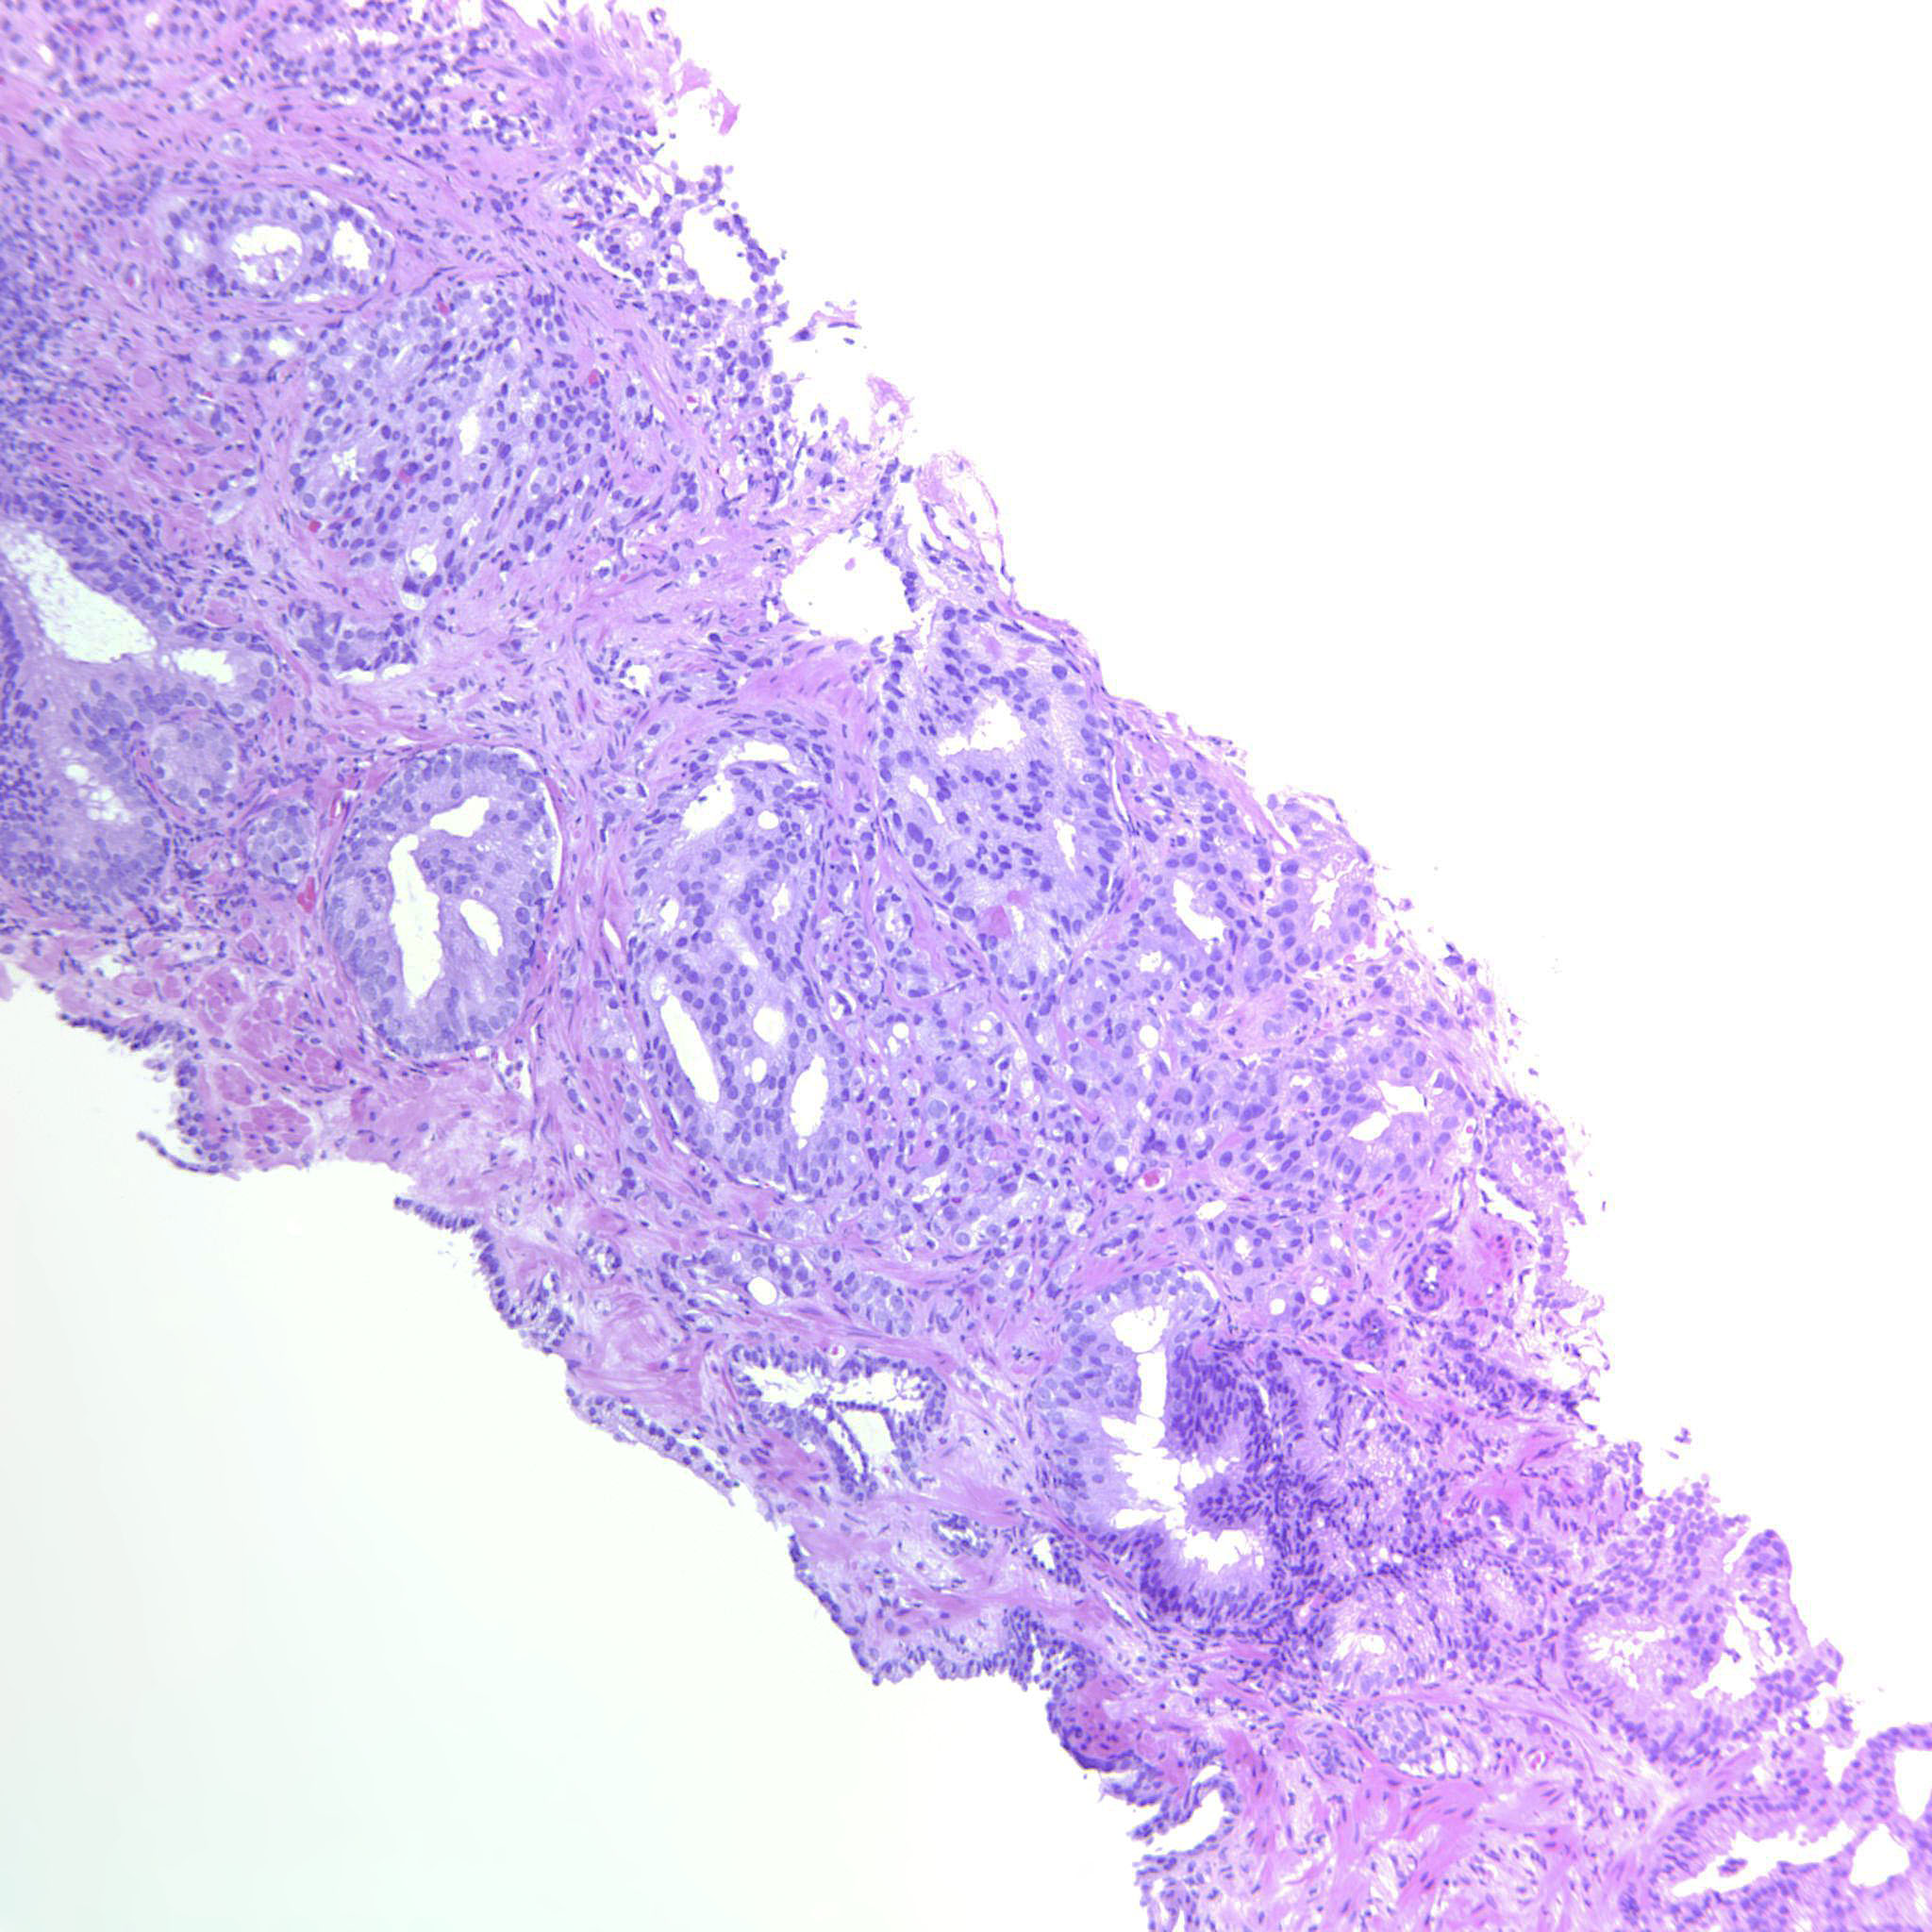

Consensus grade: GS 4+4=8 (ISUP 4)

Case description (by case creator):

Large cribriform sheets and also tightly packed poorly formed glands. Some seem to be solid nests or single cells but not convincing for GP5.